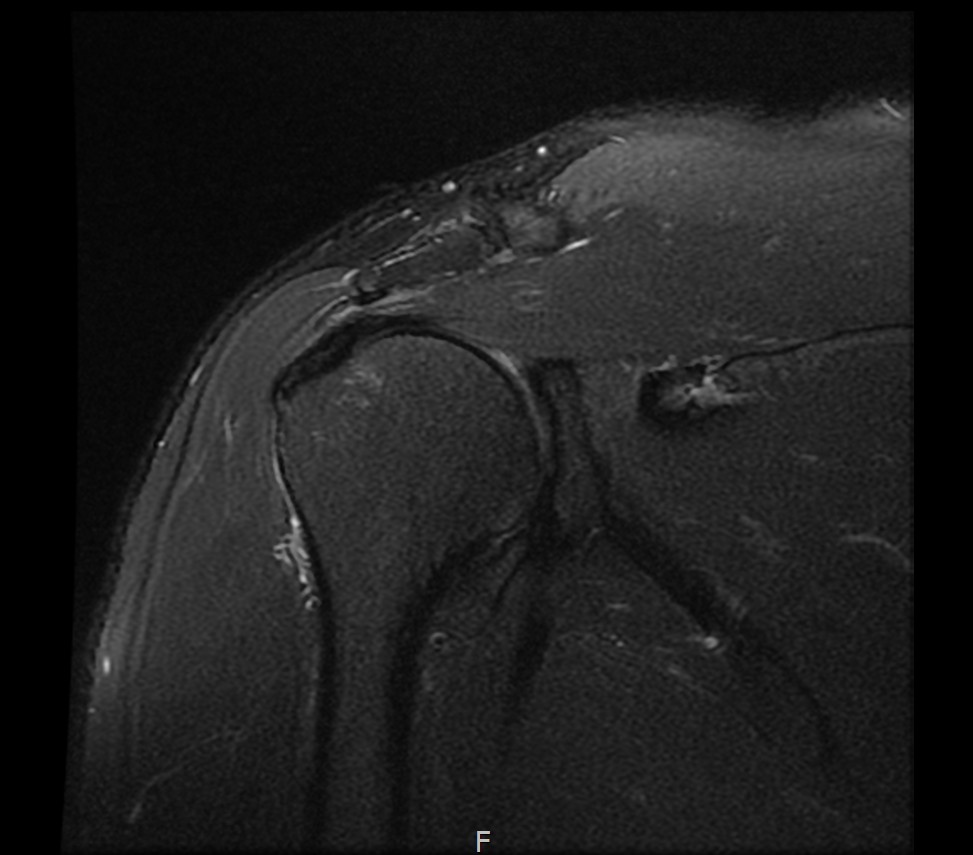

MRI를 검토해보았습니다.

회전근개 극상건의 점액낭면측(bursal-side) 부분파열. 처음보다 파열 범위가 약간 넓어져 있었고, 인대가 얇아진 소견도 보였습니다.

6개월 후 MRI로 인대 두께 확인

6개월 후 MRI: 인대 두께 5.8mm (1.6mm 증가)

6개월 후 MRI: 인대 두께 6.2mm (1.7mm 증가)